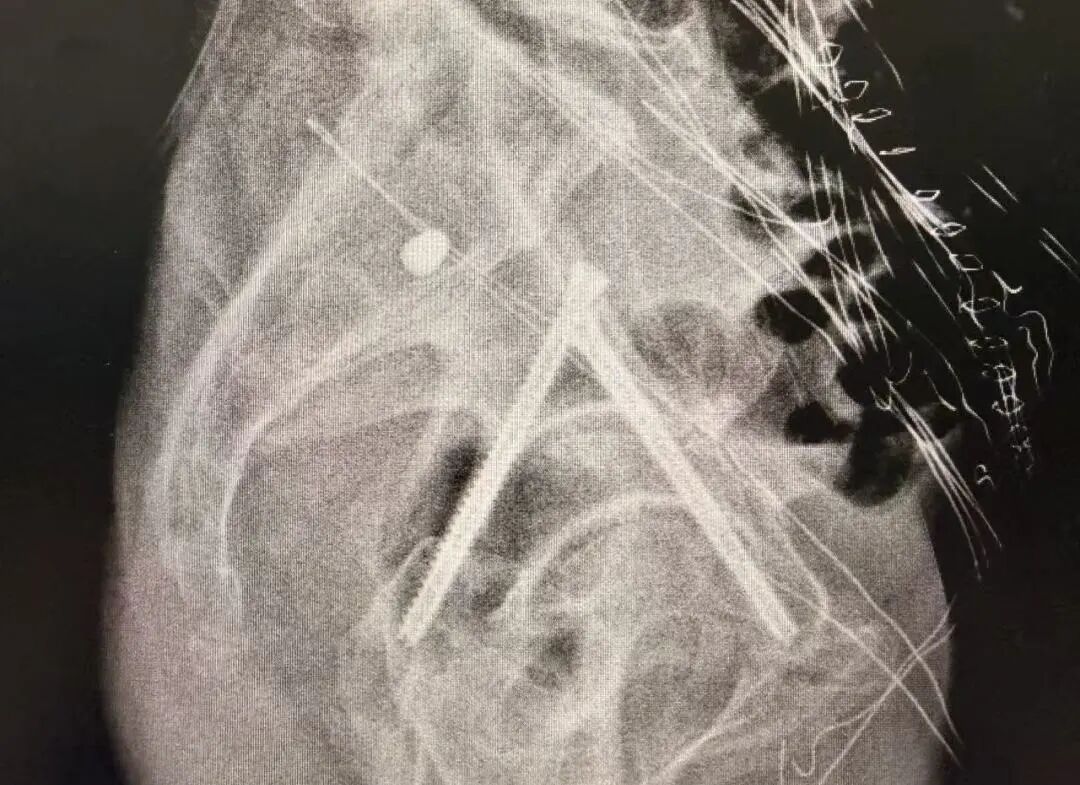

术前

团队通过三维影像重建,为患者量身定制手术路径,数据导入系统后生成个性化复位方案。